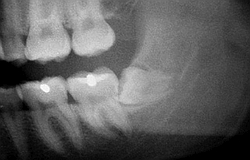

Bilder: Nur auf dem Röntgenbild ist der Störenfried zu erkennen

der Zahn will rauswachsen Durch den Druck schmerzt es sehr

Retinierte oder verlagerte Weisheitszähne haben keinen Platz im Kiefer. Beim aussichtslosen Versuch trotzdem herauszukommen, können Sie Nachbarzähne auflösen und schädigen oder das "das Gebiss verschieben. "Sie können auch Schmerzschübe auslösen . Deshalb sollten Sie besser entfernt werden. Wie bei jeder Operation muss vorher über mögliche Risiken wie Nervausfälle, Verletzung der Kieferhöhle und die Gefahr der Nachblutung aufgeklärt werden, selbst wenn die Wahrscheinlichkeit sehr gering erscheint. Die Risiken werden den voraussichtlichen Schäden durch den Verbleib des Weisheitszahnes gegenübergestellt. Erst nach Aufklärung und Einwilligung durch den Patienten wird der Eingriff durchgeführt. Bereits durchgebrochene Weisheitszähne sind oft schadhaft, da der Patient sie zum Putzen mit der Bürste fast nicht erreichen kann. Bevor sie als "Schmutzreservoir" auch den Nachbarzahn mit Karies anstecken sollte man sie besser ziehen. In diesem Fall verläuft die Extraktion einfacher mit weniger Risiken. Verhalten nach einer Operation. Manchmal ist der Zahn schon vorher inifziert oder entzündet sich nach der OP durch die Mundbakterien in diesem Fall muss die Naht wieder geöffnet werden und ein Medikamentenstreifen zum Ablass von Sekret und Eiter eingebracht werden.